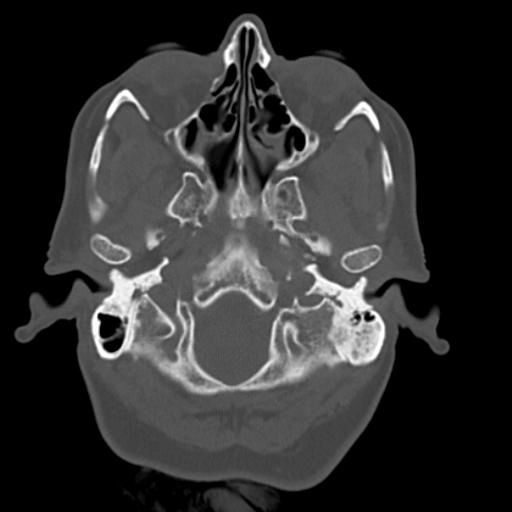

U hạt cholesterol (Cholesterol granulomas)